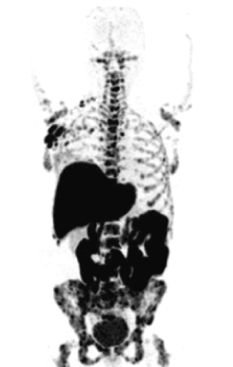

PET הינה טכניקת דימות ברפואה גרעינית, המאפשרת להתבונן בתהליכים מטבוליים ומולקולריים בגוף, ולקבל אודותם מידע כמותי. גלאי הסורק מזהים זוגות של פוטונים בעלי אנרגיה ייחודית,

המחלקה לרפואה גרעינית עוסקת במתן רדיו-תרופות לצרכי טיפול, אבחון ומחקר. במרבית המקרים, הרדיו-תרופה ניתנת בהזרקה לוריד לצורך האבחון או הטיפול. לאחר פיזור החומר גוף והגעתו

רדיו-תרופות משמשות לטיפול ולאבחון של מגוון מחלות באופן לא פולשני. רדיו-תרופה הינה מולקולה, המורכבת משני רכיבים עיקריים: האחד רדיואקטיבי והשני בעל אופי ביוכימי, ותפקידו לכוון